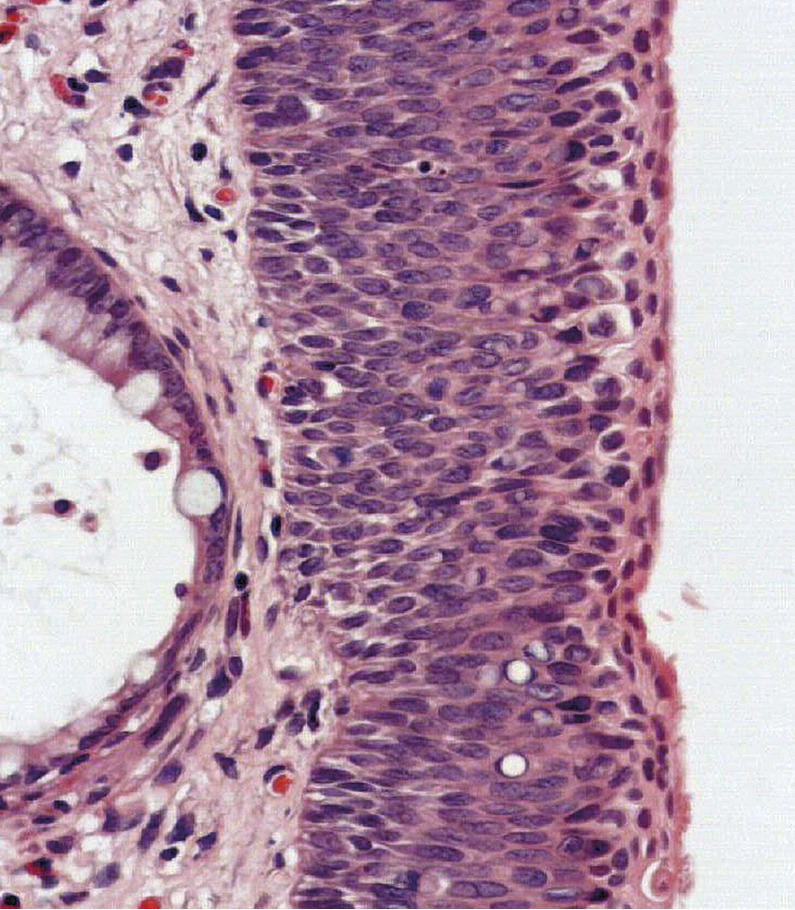

Les principaux diagnostics différentiels sont le psoriasis, l’eczéma, les mycoses ainsi que la maladie de Paget et la papulose bowenoïde. Le diagnostic est histologique (fig. 2).